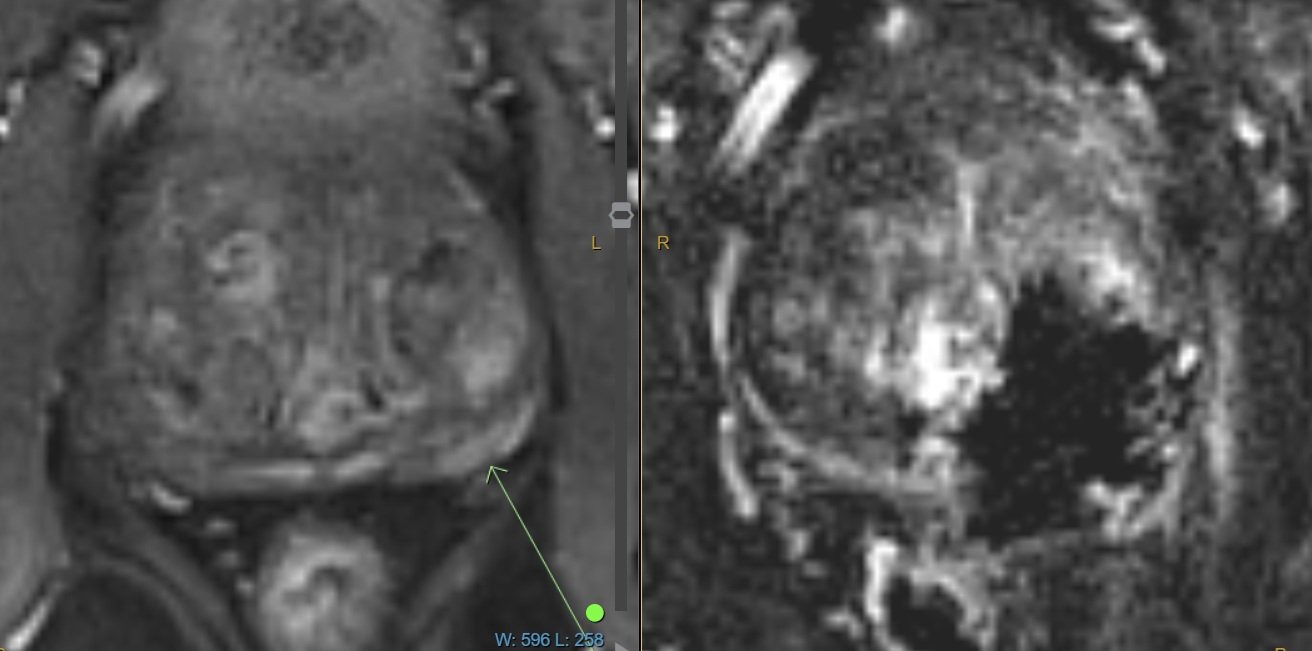

MRI Pre and Post NanoKnife Treatment

Left: MRI pre-treatment showing the prostate tumour.

Right: MRI 2 weeks post-treatment showing the treatment coverage is satisfactory.